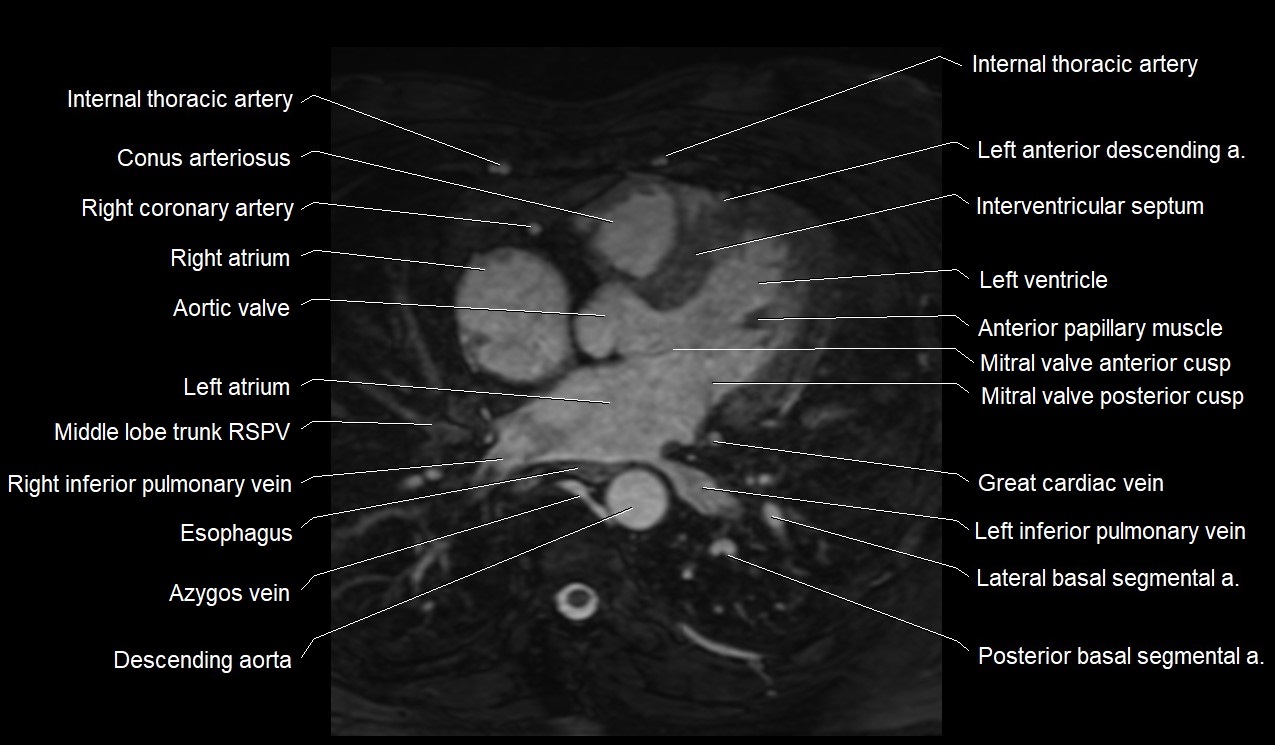

MRI image